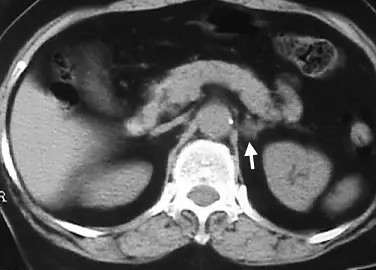

電腦斷層影像檢查如下圖,關於圖中箭號所指,最可能為下列何者?

- 影像掃描參數與切面:此為腹部無對比劑(Non-contrast)電腦斷層橫斷面影像,因為腹主動脈(Aorta)與下腔靜脈(IVC)的密度與周圍肌肉相近,無明顯亮白(高密度)的顯影劑特徵。

- 解剖構造定位:

- 中央可見腹主動脈位於椎體前方,其兩側有橫膈腳(Crura of diaphragm)包覆。

- 影像右側(病患左側)可見左側腎臟的上極。

- 病灶前方有胰臟橫跨,胰臟後方有脾靜脈。

- 病灶特徵:箭號所指處為一界線清楚、呈現相對低密度(Low attenuation)的結節狀腫塊。

- 位置:位於左側腎臟上極的內前側、左側橫膈腳的外側、胰臟尾部及脾臟血管的後方。這個特定的解剖空間正是**左側腎上腺(Left adrenal gland)**的所在位置。

- 密度:腫塊呈現偏暗的低密度,暗示其內部含有豐富的脂質(Lipid-rich),這在影像學上是良性腎上腺腺瘤的高度懷疑特徵。